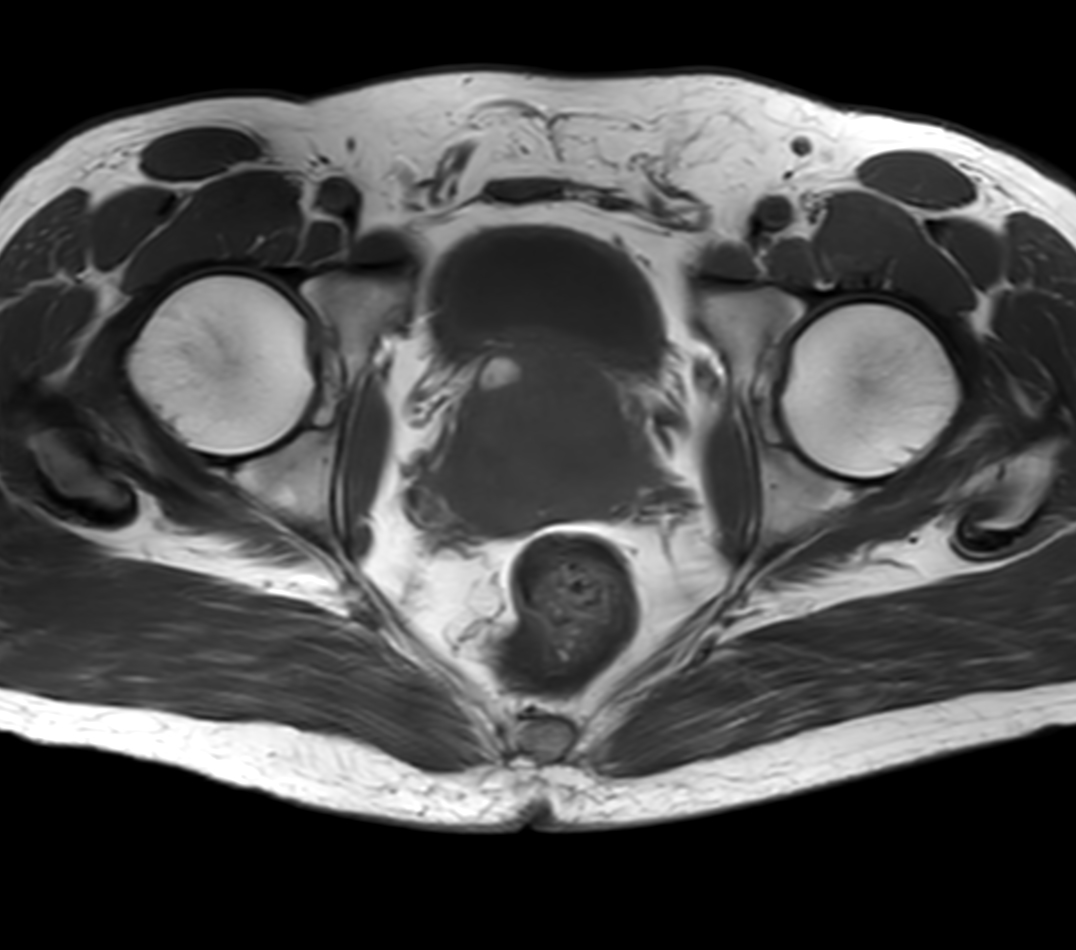

Axial T1w TSE with Compressed SENSE